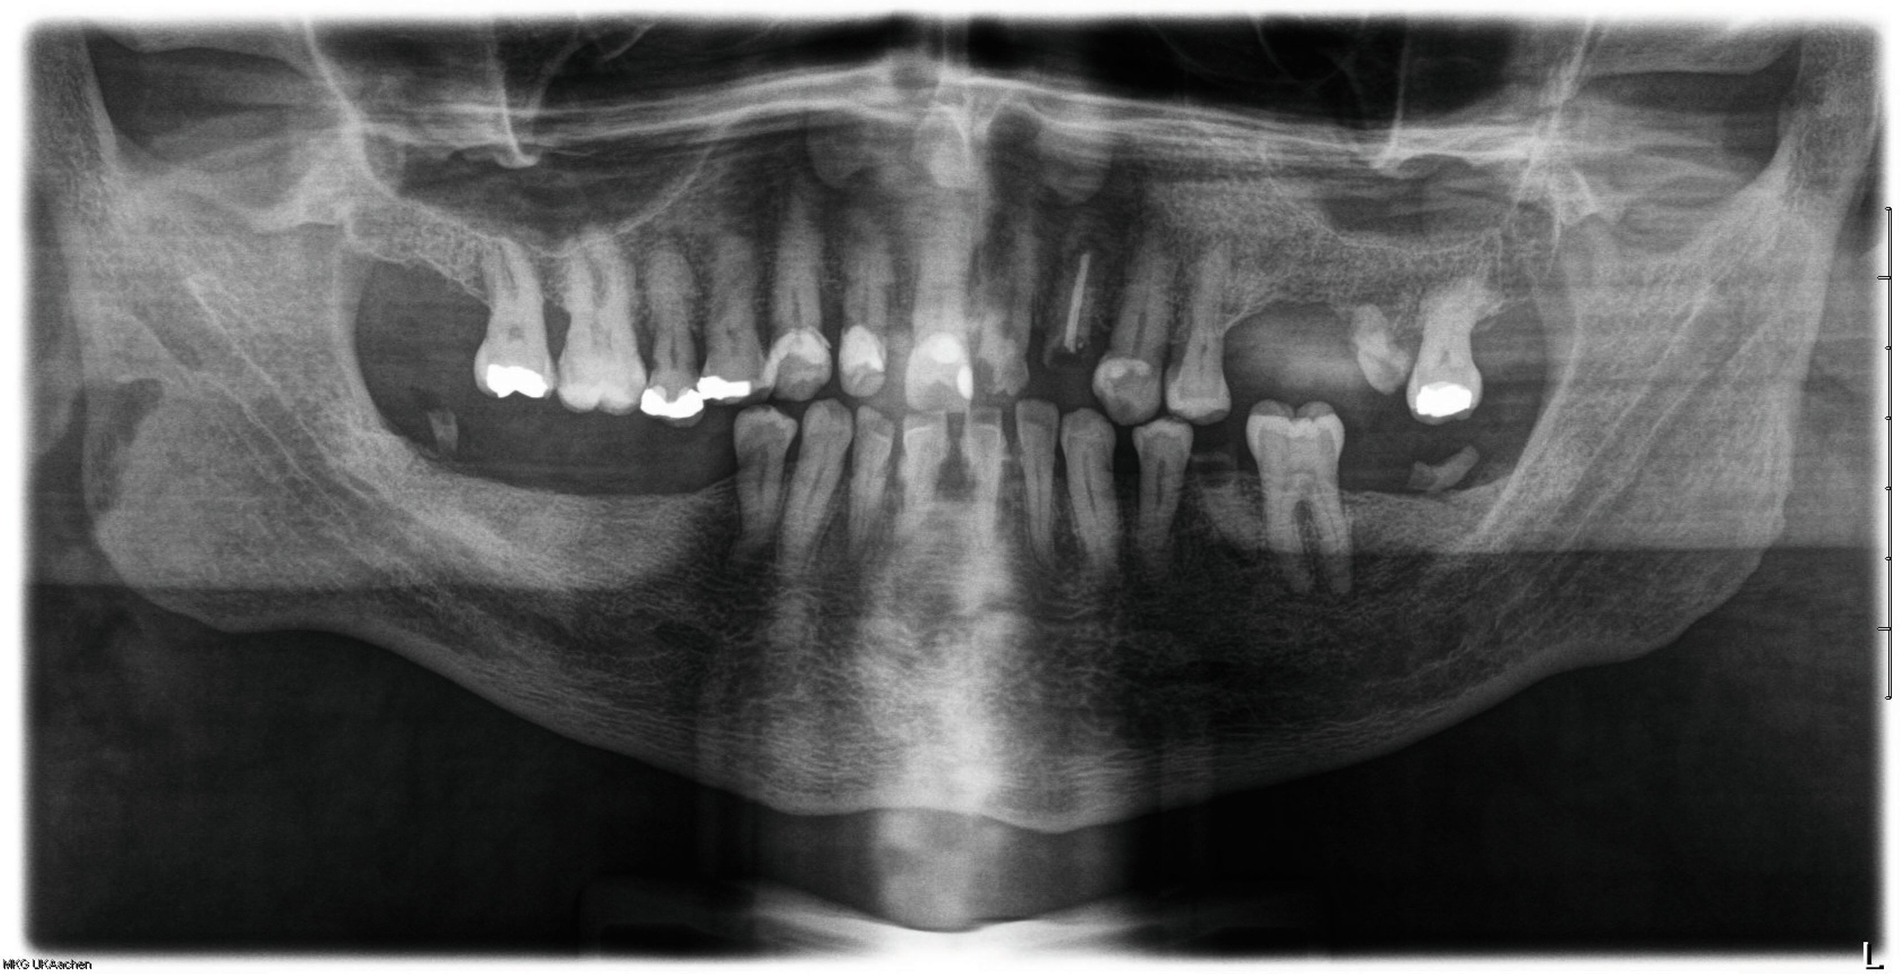

In der durchgeführten Orthopantomografie zeigten sich multiple nicht erhaltungswürdige Zähne, jedoch ohne eindeutigen dentalen Fokus. Zur weiteren Diagnostik führten wir eine Computertomografie durch. Dabei zeigte sich eine scharf abgrenzbare, randständig deutlich Kontrastmittel-anreichernde, insgesamt inhomogen kontrastierte Raumforderung submental bis suprahyoidal von circa 6,9 cm x 5,1 cm x 3,9 cm Größe. Es gab keinen Hinweis auf lokal destruierendes Wachstum oder Filiarisierung. Wie schon in der auswärtig durchgeführten Schilddrüsensonografie und -szintigrafie war auch in der Computertomografie das Schilddrüsenparenchym kaum abgrenzbar.